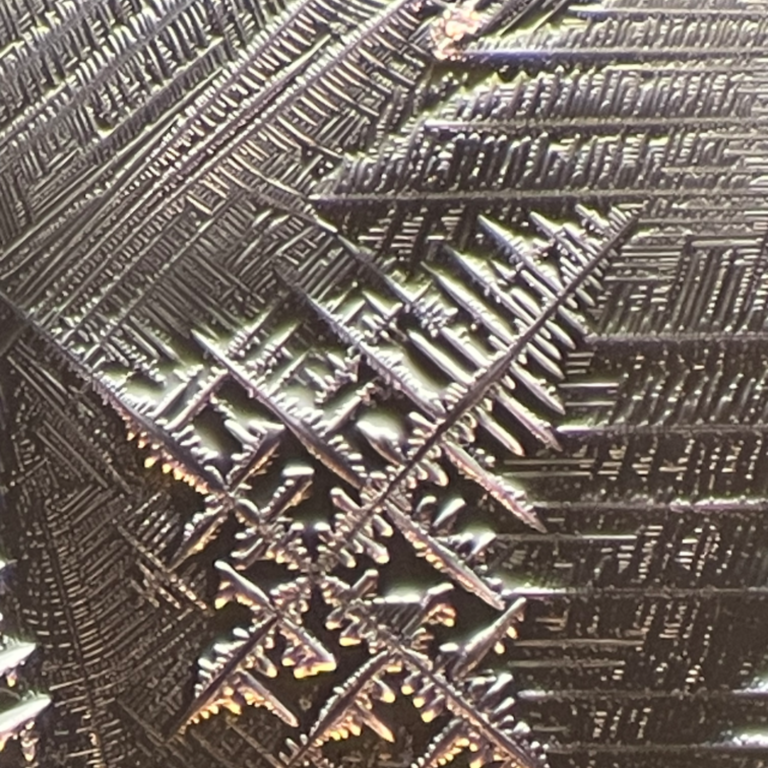

Homöopathie Forschung Kristallisationsbilder

Untersuchungen von humanen Blut und Reaktion auf homöopathische Potenzen in einem Konzentrat.

Jan.

2015